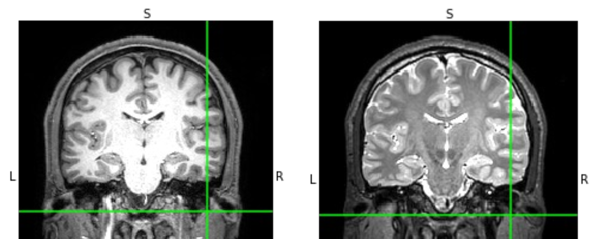

We use a volume conductor model to simulate the electric field distribution in a patient’s brain during TMS. Such a model factors in tissue conductivity, individualized head anatomy, and TMS coil parameters, optimizing predictions based on variations in skull thickness and tissue boundaries. Rooted in Maxwell’s equations, the model accounts for the coil’s size, shape, and orientation, as well as stimulation parameters, influencing the strength and characteristics of the induced electric field. Most of the tools that are available for realistic field calculations rely on methods such as FEM and head models that accurately capture the important anatomical features. We use the SimNIBS library Thielscher et al. (2015) for head model reconstruction and for personalized E-Field simulations. We first create a subject-specific tetrahedral head mesh from T1-weighted and T2-weighted magnetic resonance (MR) scans using a bash script “charm” Puonti et al. (2020). The generation of the head model is the most time-consuming step and takes hrs. The final meshes contain around nodes and tetrahedra (see Fig. 8), divided into different tissue classes. After the generation of a volume head model, FEM solvers are used to calculate the cortical distribution of electric fields in response to different TMS coil positions, intensities, and orientations.

Our simulations aim to generate TMS induced E-field datasets of depressed patients with the coil centered at their dorsolateral prefrontal cortex (DLPFC) coordinates with different coil angles. The goal is to study the performance of our method in generalizing the distributions of E-Field over different coil angles and different brain regions in real time. We consider simulating E-Fields mapped to NIfTI volume slices which accounts for each patient’s unique functional neuroanatomy and cortical folding patterns. The coil is centered at the DLPFC coordinate of an individual pointing posteriorly towards different angles with angle resolution within a circle formed by considering gray matter vertices within a distance of mm and clustering the vertices into clusters using k-means.

For model training, we consider T1w and T2w images of treatment resistant depressed patients undergoing accelerated trials at Weill Cornell Medicine, Cornell University for head model reconstruction. We use their DLPFC coordinates as the coil target and consider coil orientations determined by the different angles. The coil model used was Magventure Cool-B65 and therefore we set stimulation intensity to Drakaki et al. (2022) consistent with TMS treatment levels. The coil-to-cortex distance was set to mm.

Transforming E-Field Simulations into Image Space. The outcomes of E-Field simulations are saved in both Gmsh and NIfTI formats, with the latter mapping the E-Field values onto subject-specific volumes. To process this data, we utilize the NiBabel Python package, which allows us to access the E-Field values mapped onto NIfTI volumes as NumPy arrays. These arrays match the orientation and dimensions of 3D brain imaging data. For visualization, we generate 2D images by slicing through the 3D imaging data volume, with each slice representing a distinct cross-sectional view of the subject at a precise location. Using Matplotlib, we then save these visualized E-Field mappings as RGBA image files. Through this method, we effectively convert E-Field simulation outputs into image data ( pixels).